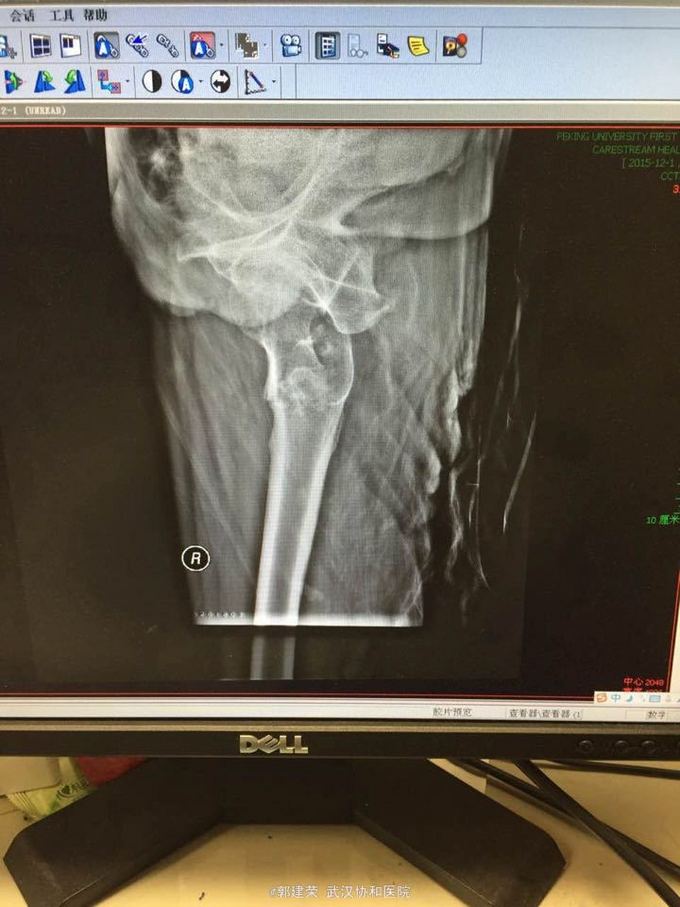

患者,男,76岁 主诉:摔倒后髋部疼痛2天余 病史:患者2天前摔倒,臀部着地,摔倒后自感右侧髋部疼痛,右下肢不能活动,不能直立,伴右下肢外测疼痛,不伴下肢麻木,发冷等感觉。为求诊治,患者遂来我院门诊,门诊行x线,示:右侧股骨粗隆间骨折。闷着以“右侧股骨粗隆间骨折”收入我科。

查体:右下肢外旋畸形,角度大于90°,略缩短,双下肢足背动脉搏动正常,感觉运动正常 辅查:门诊行x线,示:右侧股骨粗隆间骨折

诊断:右侧股骨粗隆间骨折 治疗:完善术前检查,持续皮牵引,择期行闭合复位内固定术(防旋型股骨近端髓内钉(PFNA)内固定方法),术后复查X线